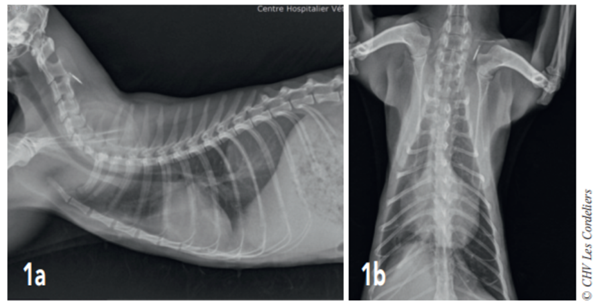

figure 2

Fig. 2a – Radiographie thoracique de profil droit du02/09/2017 (J+21 jours) : cardiomégalie (VHSM 9,5 ; VU : 7, 5 ± 0,3 A.L. Lister), épanchement pleural et consolidation du lobe moyen droit.

Fig. 2b – Radiographie thoracique de face du 02/09/2017 (J+21 jours) : cardiomégalie (silhouette cardiaque > 2/3 de la largeur thoracique), épanchement pleural (scissure pleurale) et consolidation du lobe moyen droit

J+21 jours : le chat est en bon état général mais présente des épisodes de dyspnée (FR : 40-44 rpm). Les radiographies (Fig. 2a et 2b) montrent une cardiomégalie (VHS = 9,5) avec un épanchement pleural (scissure interlobaire) et une consolidation du lobe pulmonaire moyen droit : ces images sont compatibles avec une atélectasie pulmonaire ne permettant pas d’exclure un processus néoplasique ; la vascularisation artérielle pulmonaire est dans les normes.